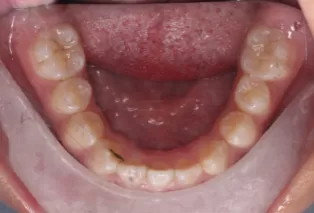

Photos intra-orales